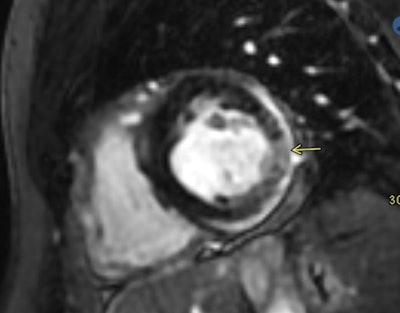

Additional case of myocarditis in a young male (26-30 years old) presenting to the hospital three days after a second mRNA Covid vaccine. The patient underwent a cardiac MR ten days post vaccine; images above show a focal area of edema and delayed enhancement in the mid-inferolateral segment. There is also a trace pericardial effusion with enhancement of the pericardium indicating pericarditis in addition to the myocarditis. Images courtesy of Dickey team co-author Dr. David Gerson of University of Massachusetts Medical School in Worcester.Although these case studies represent a very small set of patients, they may help shed light on patient reactions to COVID-19 vaccines -- with advanced imaging playing a crucial role, according to Shaw's group.